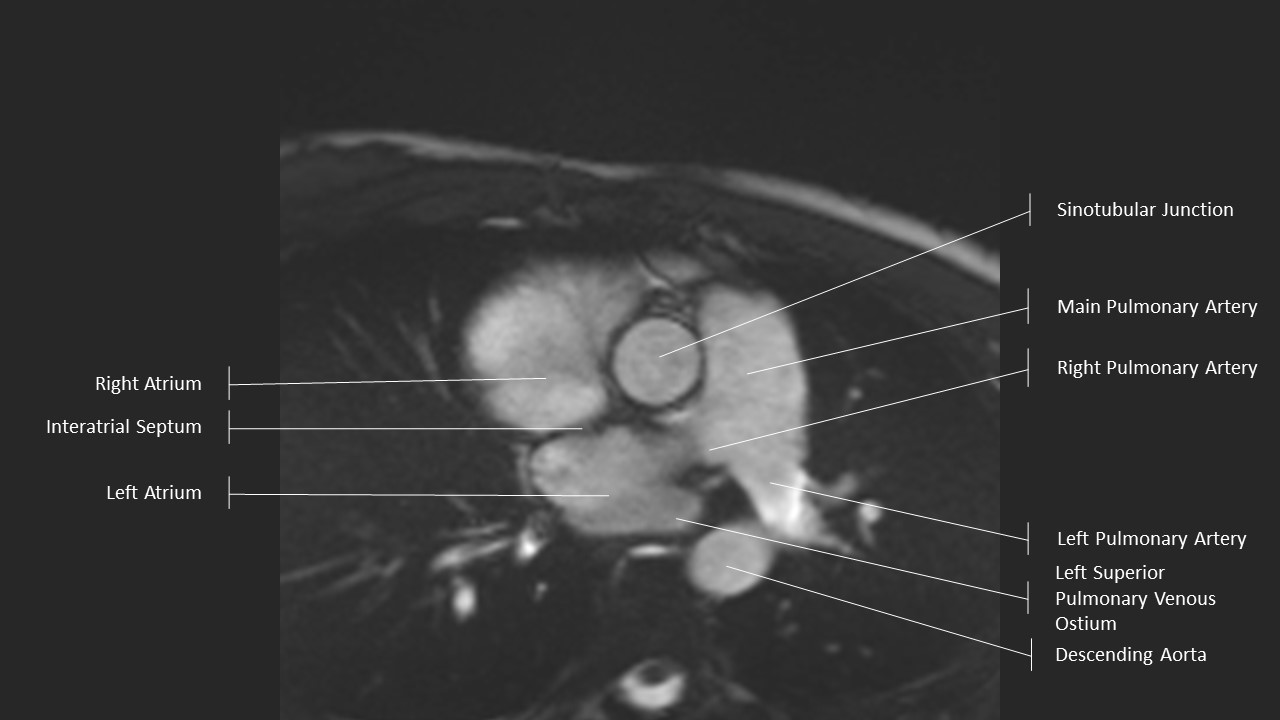

Aortic Root Series:

Sinotubular Junction

Aortic Root Series